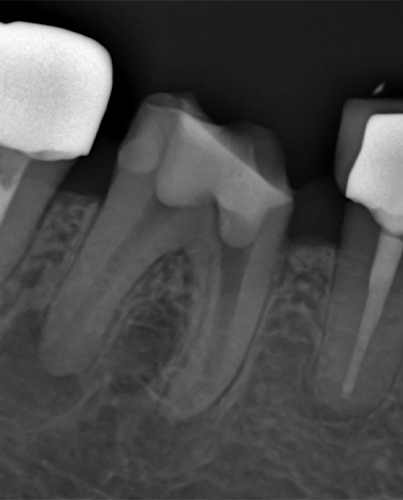

삭제의 핵심은

정밀함에 있습니다

치아를 지키는 치료는

얼마나 정확히 다루느냐의 문제입니다.

연세일등치과는 최대 보존을 단순한 목표가 아닌

정밀한 진단과 설계의 결과물로 봅니다.

건강한 부위와 손상 부위를 면밀히 구분하고,

필요한 만큼만 조심스럽게 다듬어

치아 본연의 구조를 최대한 보존하는 치료를 진행합니다.